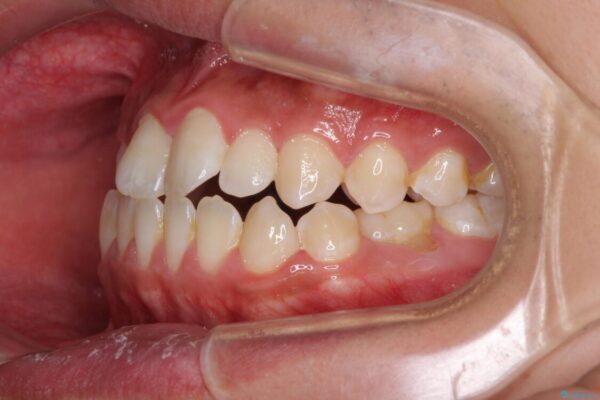

治療前

• 口元の突出感を改善 受け口傾向の咬み合わせの抜歯矯正 治療前画像